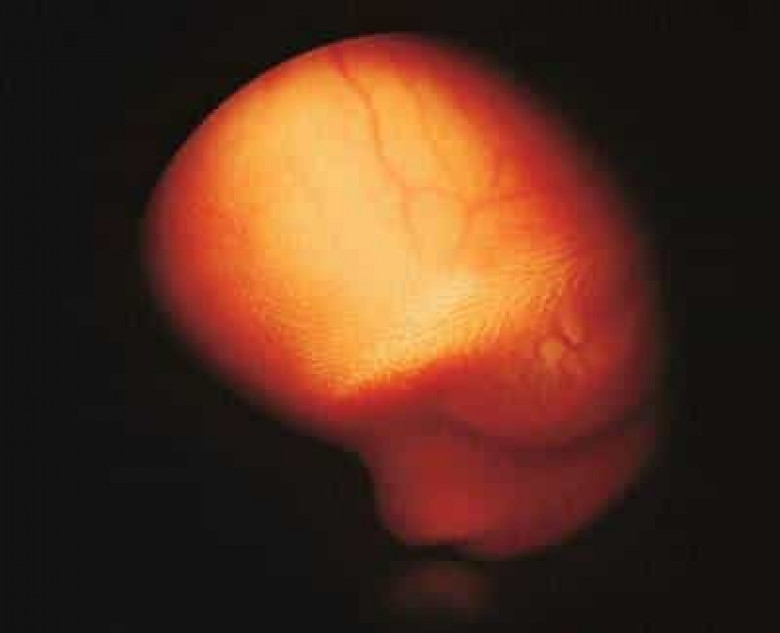

ՀԱՍԱՐԱԿՈՒԹՅՈՒՆՉիլիում բժիշկները 92-ամյա տատիկի մարմնում հայտնաբերել են 50 տարվա վաղեմության մումիֆիկացված պտուղ: Այս մասին հայտնում է La Tercera պարբերականը:

Տարեց կինը բժշկի է դիմել ընկնելուց հետո՝ որովայնային ցավերի գանգատներով: Ռենտգենը ցույց է տվել կնոջ մոտ շուրջ 50 տարի առաջ բեղմնավորված պտղի առկայություն:

30 շաբաթական պտուղն անհայտ պատճառներով դադարել է զարգանալ և չորացել է՝ կնոջ համար չստեղծելով անհարմարություններ։ Նա նույնիսկ գլխի չի ընկել իր հղիության մասին:

Բժիշկները որոշել են հանգիստ թողնել մումիան, քանի որ այն դուրս բերելու փորձերը վտանգավոր կարող էին լինել տարեց «հղիի» համար: